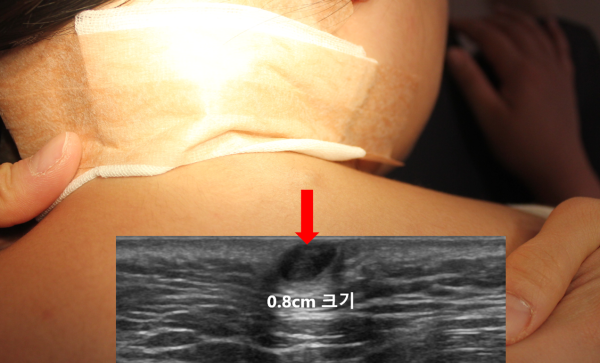

혹의 정확한 양상, 크기, 피부로 부터의 깊이, 그리고 염증 소견이 있는지 확인하기 위해 초음파 검사를 시행하였습니다.

초음파상 가로x세로의 길이가 약 0.8x0.8cm 크기인 표피낭종이었으며 염증소견은 관찰되지 않았습니다.